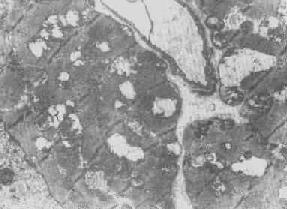

在生理状态下,随着细胞功能的升降,光面内质网(SER)的数量也呈现相应改变。但亦可出现完全相反的情况,例如在某些疾病(如淤胆)时,从形态结构上看,肝细胞光面内质网显著增生(图1-7),但其混合功能氧化酶的活性反而下降,这实际上是细胞衰竭的表现。

图1-7 肝细胞光面内质网增生伴轻度扩大 ×8000